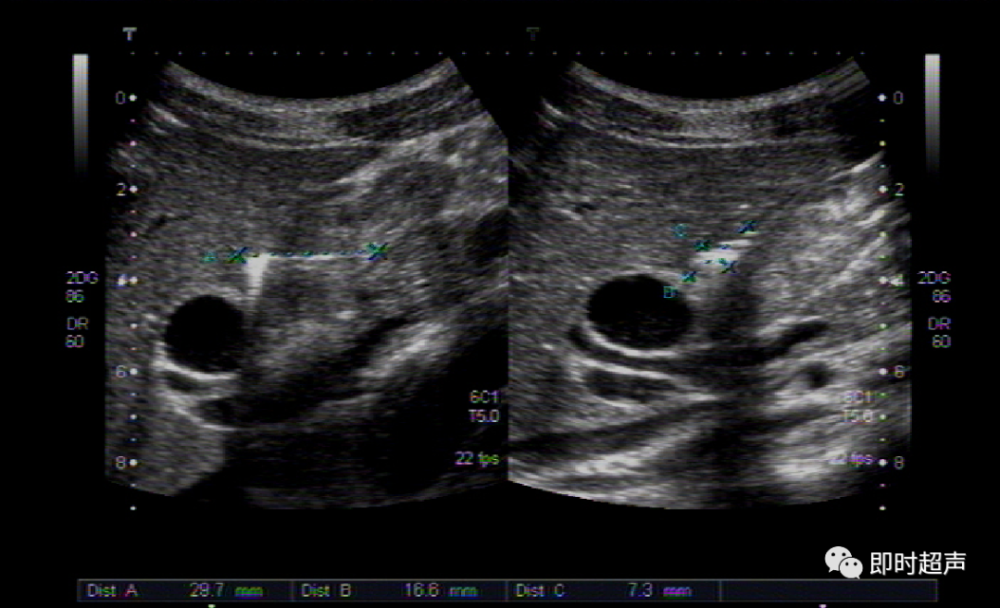

超声提示:胃窦增厚,考虑占位.